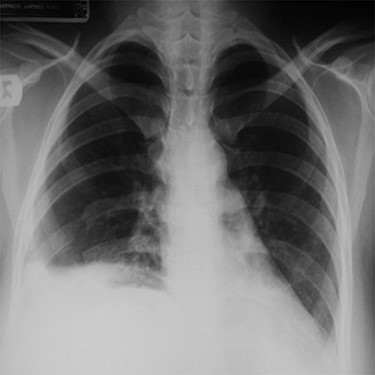

Abdominal CT scan with contrast showing the entire liver and some bowel loops occupying the right hemi-thorax.

showed the entire liver and some bowel loops in the right hemi-thorax (Fig. 2). The impression was right diaphragmatic herniation, although ruptured right hemidiaphragm was entertained despite the negative history of chest trauma.